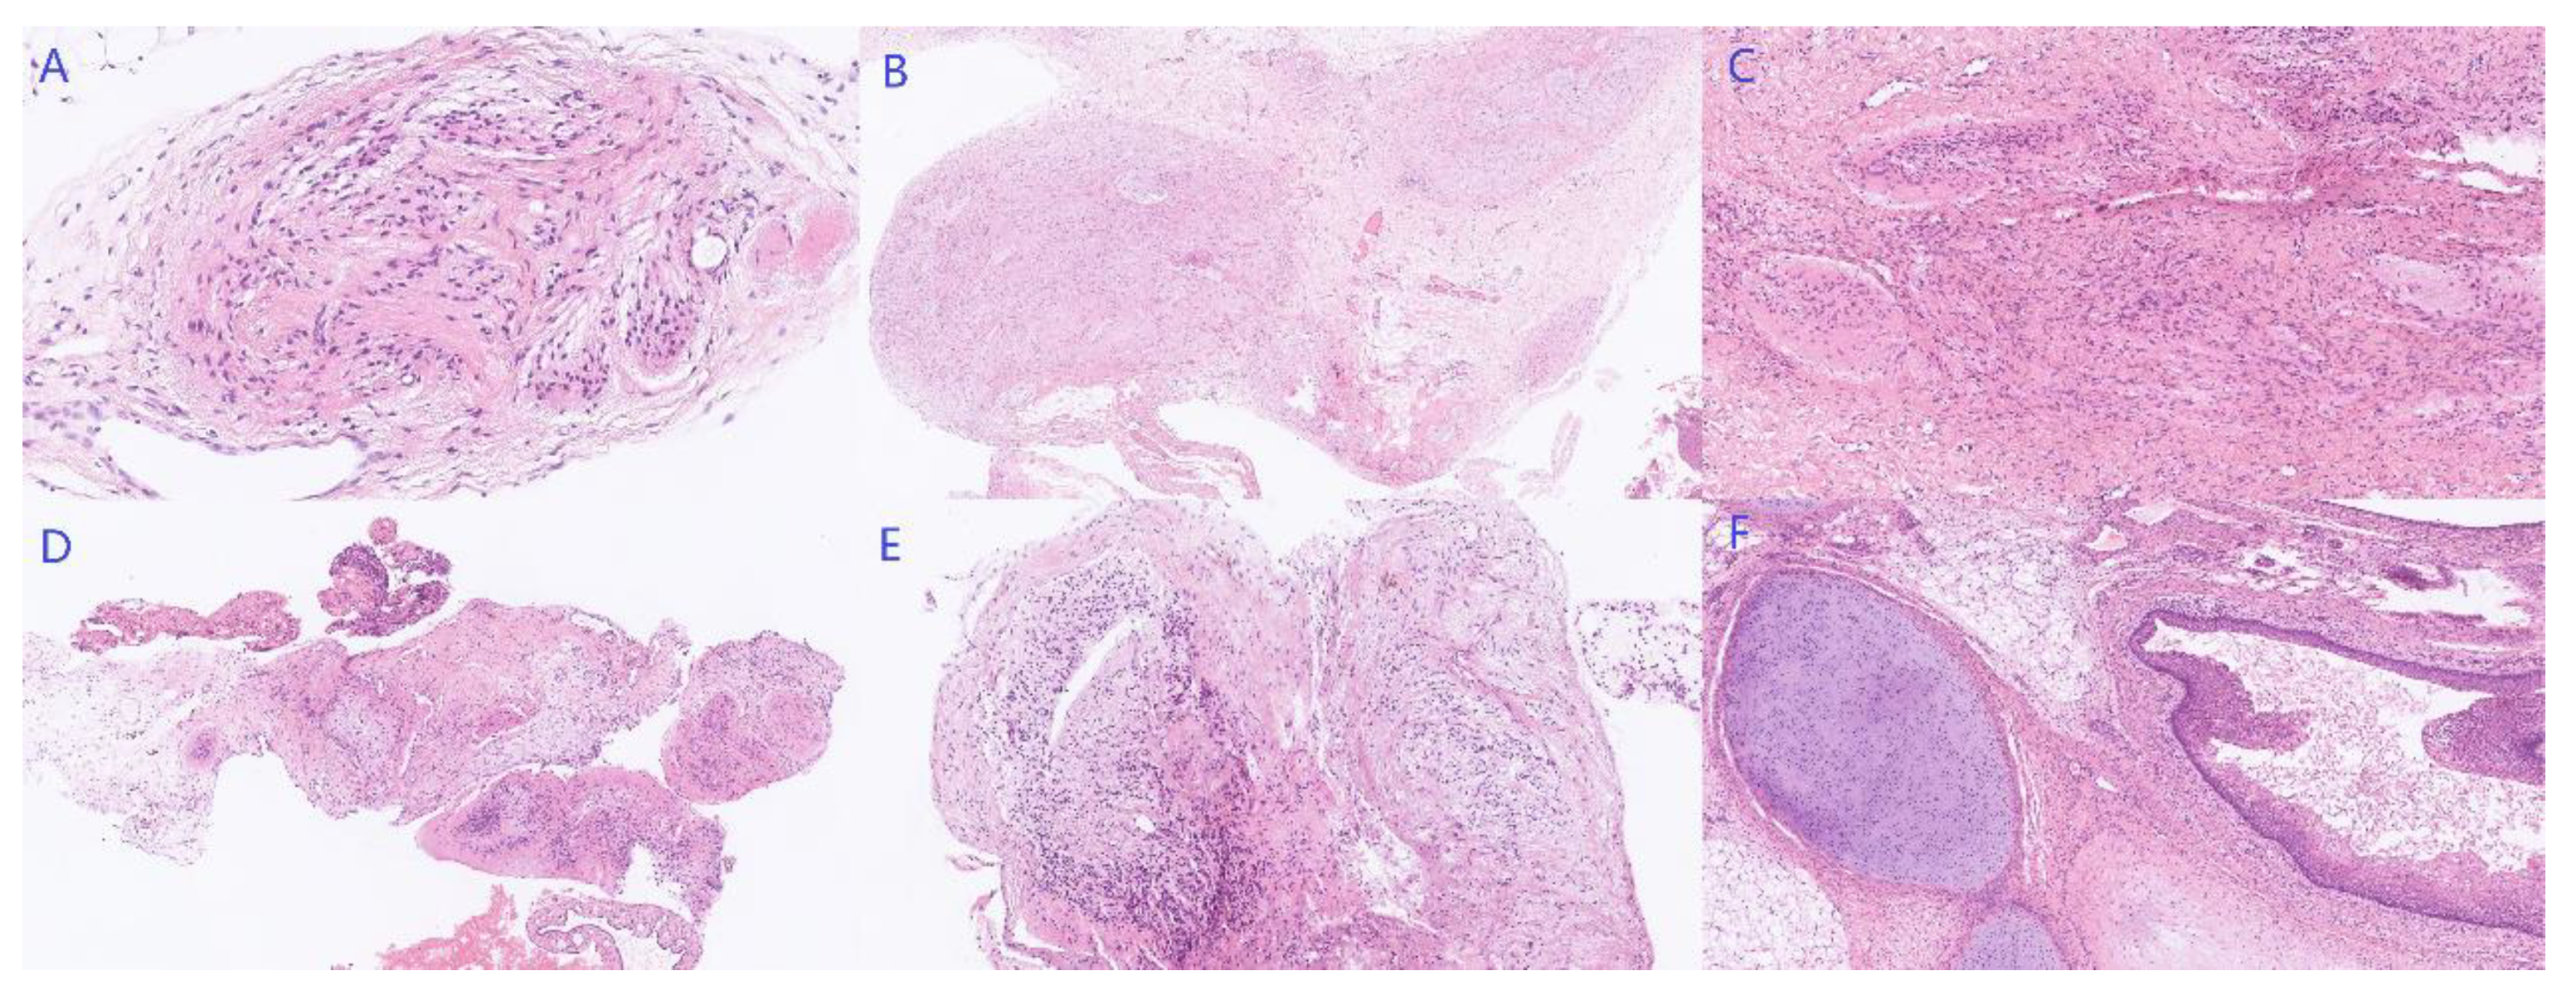

2. Case